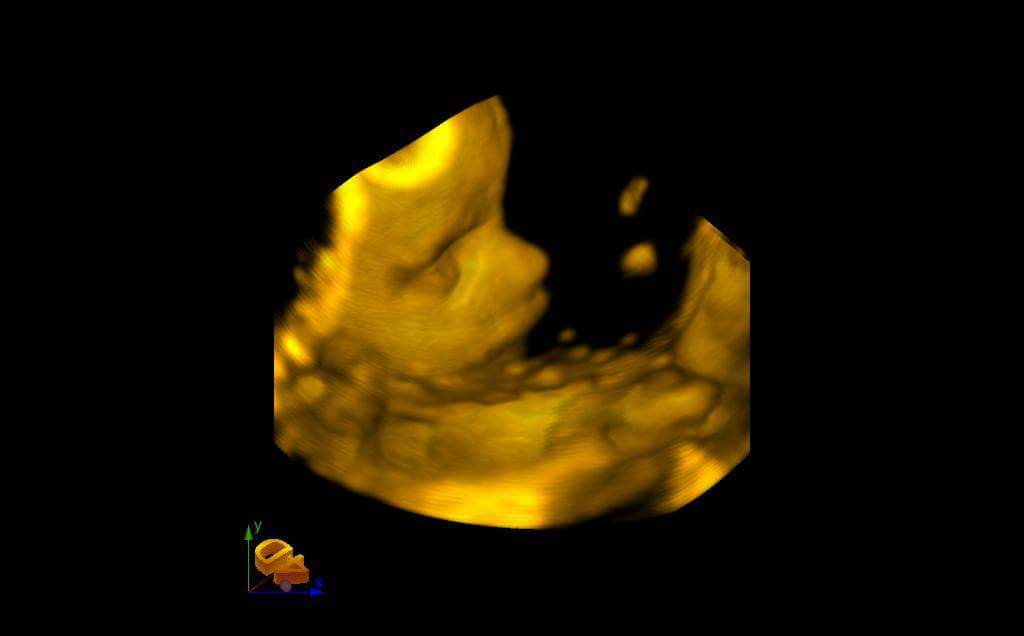

mercedes-eco2Es la última que nos envía sus ecografías. Solo tiene 18 años. Ha conseguido poder pagarse unas ecografías en 4D. Nos las ha enviado a toda la asociación. Se llama Mercemercedes-eco3des y es una de las menores de 20 años que tenemos en los cursos de la asociación. Está tan feliz que se ha puesto a estudiar. mercedes-eco4Viene a todo lo que la convocamos. Y ella también nos hace felices a nosotros. La hemos prometido que le pondríamos sus ecografias en este blog para que lo puedan ver todos los rescatadores Juan Pablo II. Como nos comentó hace dos días, parece mentira que hace 5 meses intentara abortar a su hijo. Hoy empieza su tercer trimestre de embarazo. Asociación MásFuturo